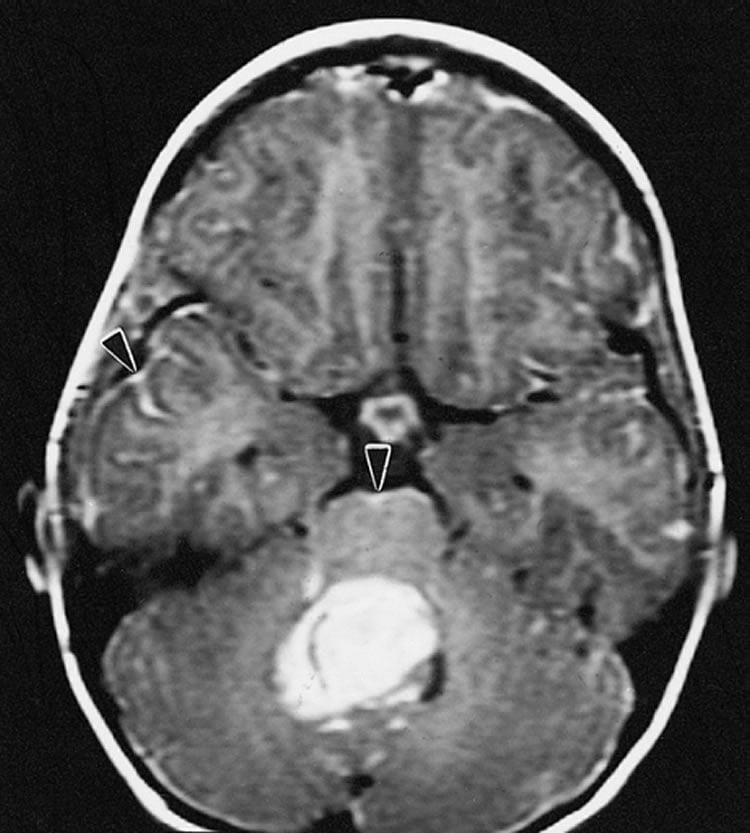

Medulloblastoma develops in the cerebellum at the base of the skull and involves four different subtypes, each with different genetic alterations. The tumor is diagnosed in as many as 400 children and adolescents annually in the U.S., making it the most common malignant pediatric brain tumor. Medulloblastoma is less common in adults, who account for about one-third of newly identified patients each year.

Image Credit: The image is credited to The Armed Forces Institute of Pathology and is in the public domain.